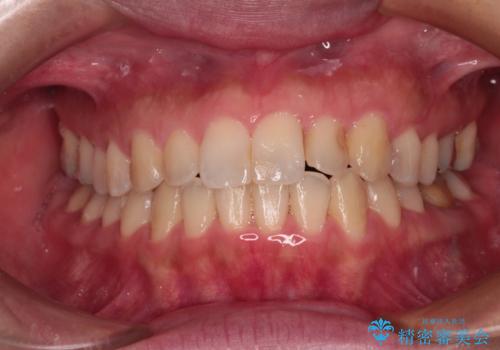

咬合平面の乱れを改善(全顎矯正歯科治療)

- 左下欠損部へのインプラント治療を希望されて来院されました。

咬合平面が乱れていたため、矯正治療によるかみ合わせの改善を行った上で、インプラント治療を行うこととしました。